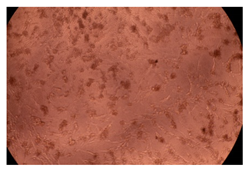

2.4. In Vitro Cytotoxicity Analysis

| Control |  |  | |

| Cop B | 10 µg/mL |  |  |

| 50 µg/mL |  |  | |

| 100 µg/mL |  |  | |

| Cop B/IMC = 10/1 (wt/wt) | 10 µg/mL |  |  |

| 50 µg/mL |  |  | |

| 100 µg/mL |  |  | |

| Cop B/Dorzolamide = 10/1 (wt/wt) | 10 µg/mL |  |  |

| 50 µg/mL |  |  | |

| 100 µg/mL |  |  | |